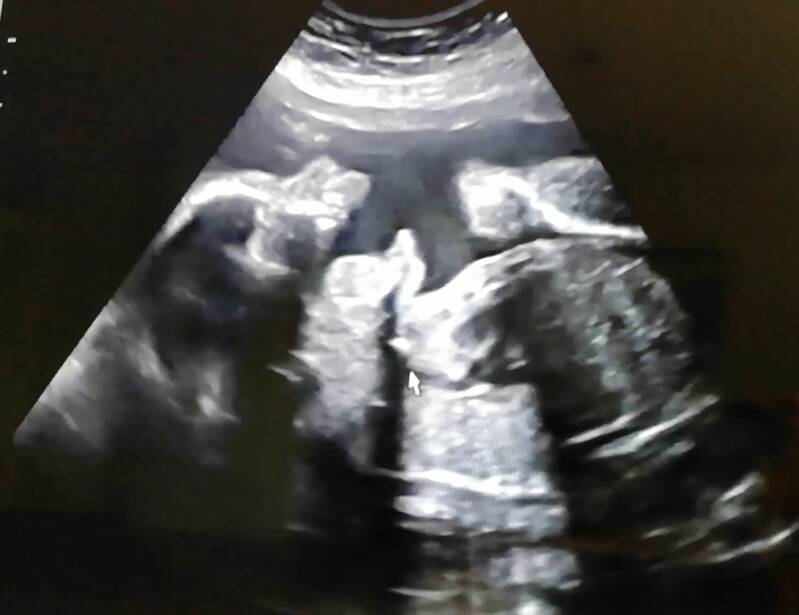

De laatste tijd merkte ik dat de angst en stress over hoe het met ons meisje gaat, steeds weer meer de overhand begon te krijgen na de vorige echo. Met gisteren als toppunt, want op een verdrietige dag voelde ik haar een aantal uur echt helemaal niet. Natuurlijk heeft de stress invloed op wat je voelt, en met 25 weken hoef je je kleintje ook nog niet eens elke paar uur te voelen. Maar dit is al weken mijn vaste rust moment op de bank waardoor zij altijd druk werd, en ik voelde, helemaal niks. Pas toen Jim thuiskwam en contact probeerde te maken, kregen we weer teken van leven. Het leek wel of ze in een diepe slaap was en zijn magic touch ervoor zorgde dat ze wakker werd. Wat een opluchting, alle alarmbellen gingen namelijk alweer af. Dus vandaag dan ook weer heel blij om na bijna 6 weken, eindelijk weer een echo te hebben gehad. Alles zag er goed uit en we mochten zelfs even getuigen van een gaapje. De volgende echo is 3 juni alweer, dus daar leven we uiteraard weer naar uit. Ik leef echt van echo naar echo.

Gaap πŸ˜‚πŸ€­πŸ˜